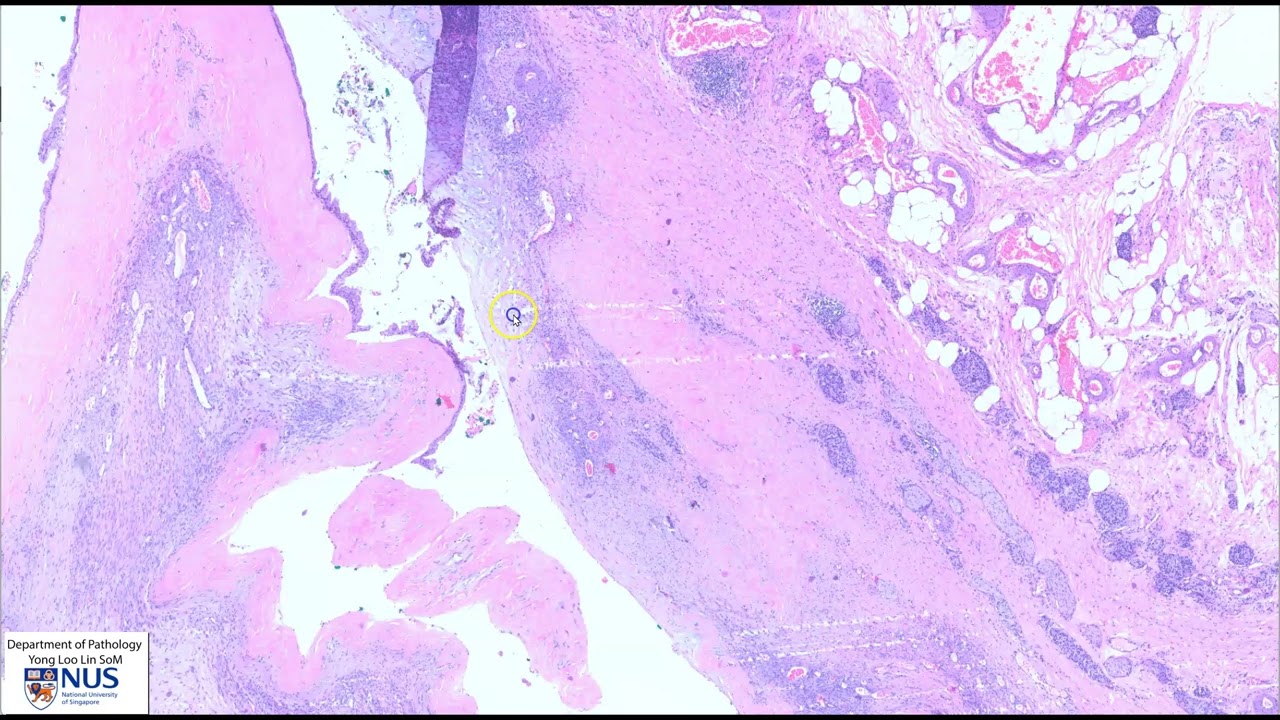

Knee synovium: Pigmented villonodular synovitis (Tenosynovial giant cell tumour)

Описание: Demonstration of gross features of pigmented villonodular synovitis/tenosynovial giant cell tumour, with clinical and microscopic correlates.